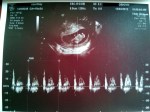

- 10w2d – Heartbeat of 165 bpm

- 10w2d – CRL of 3.91 cm